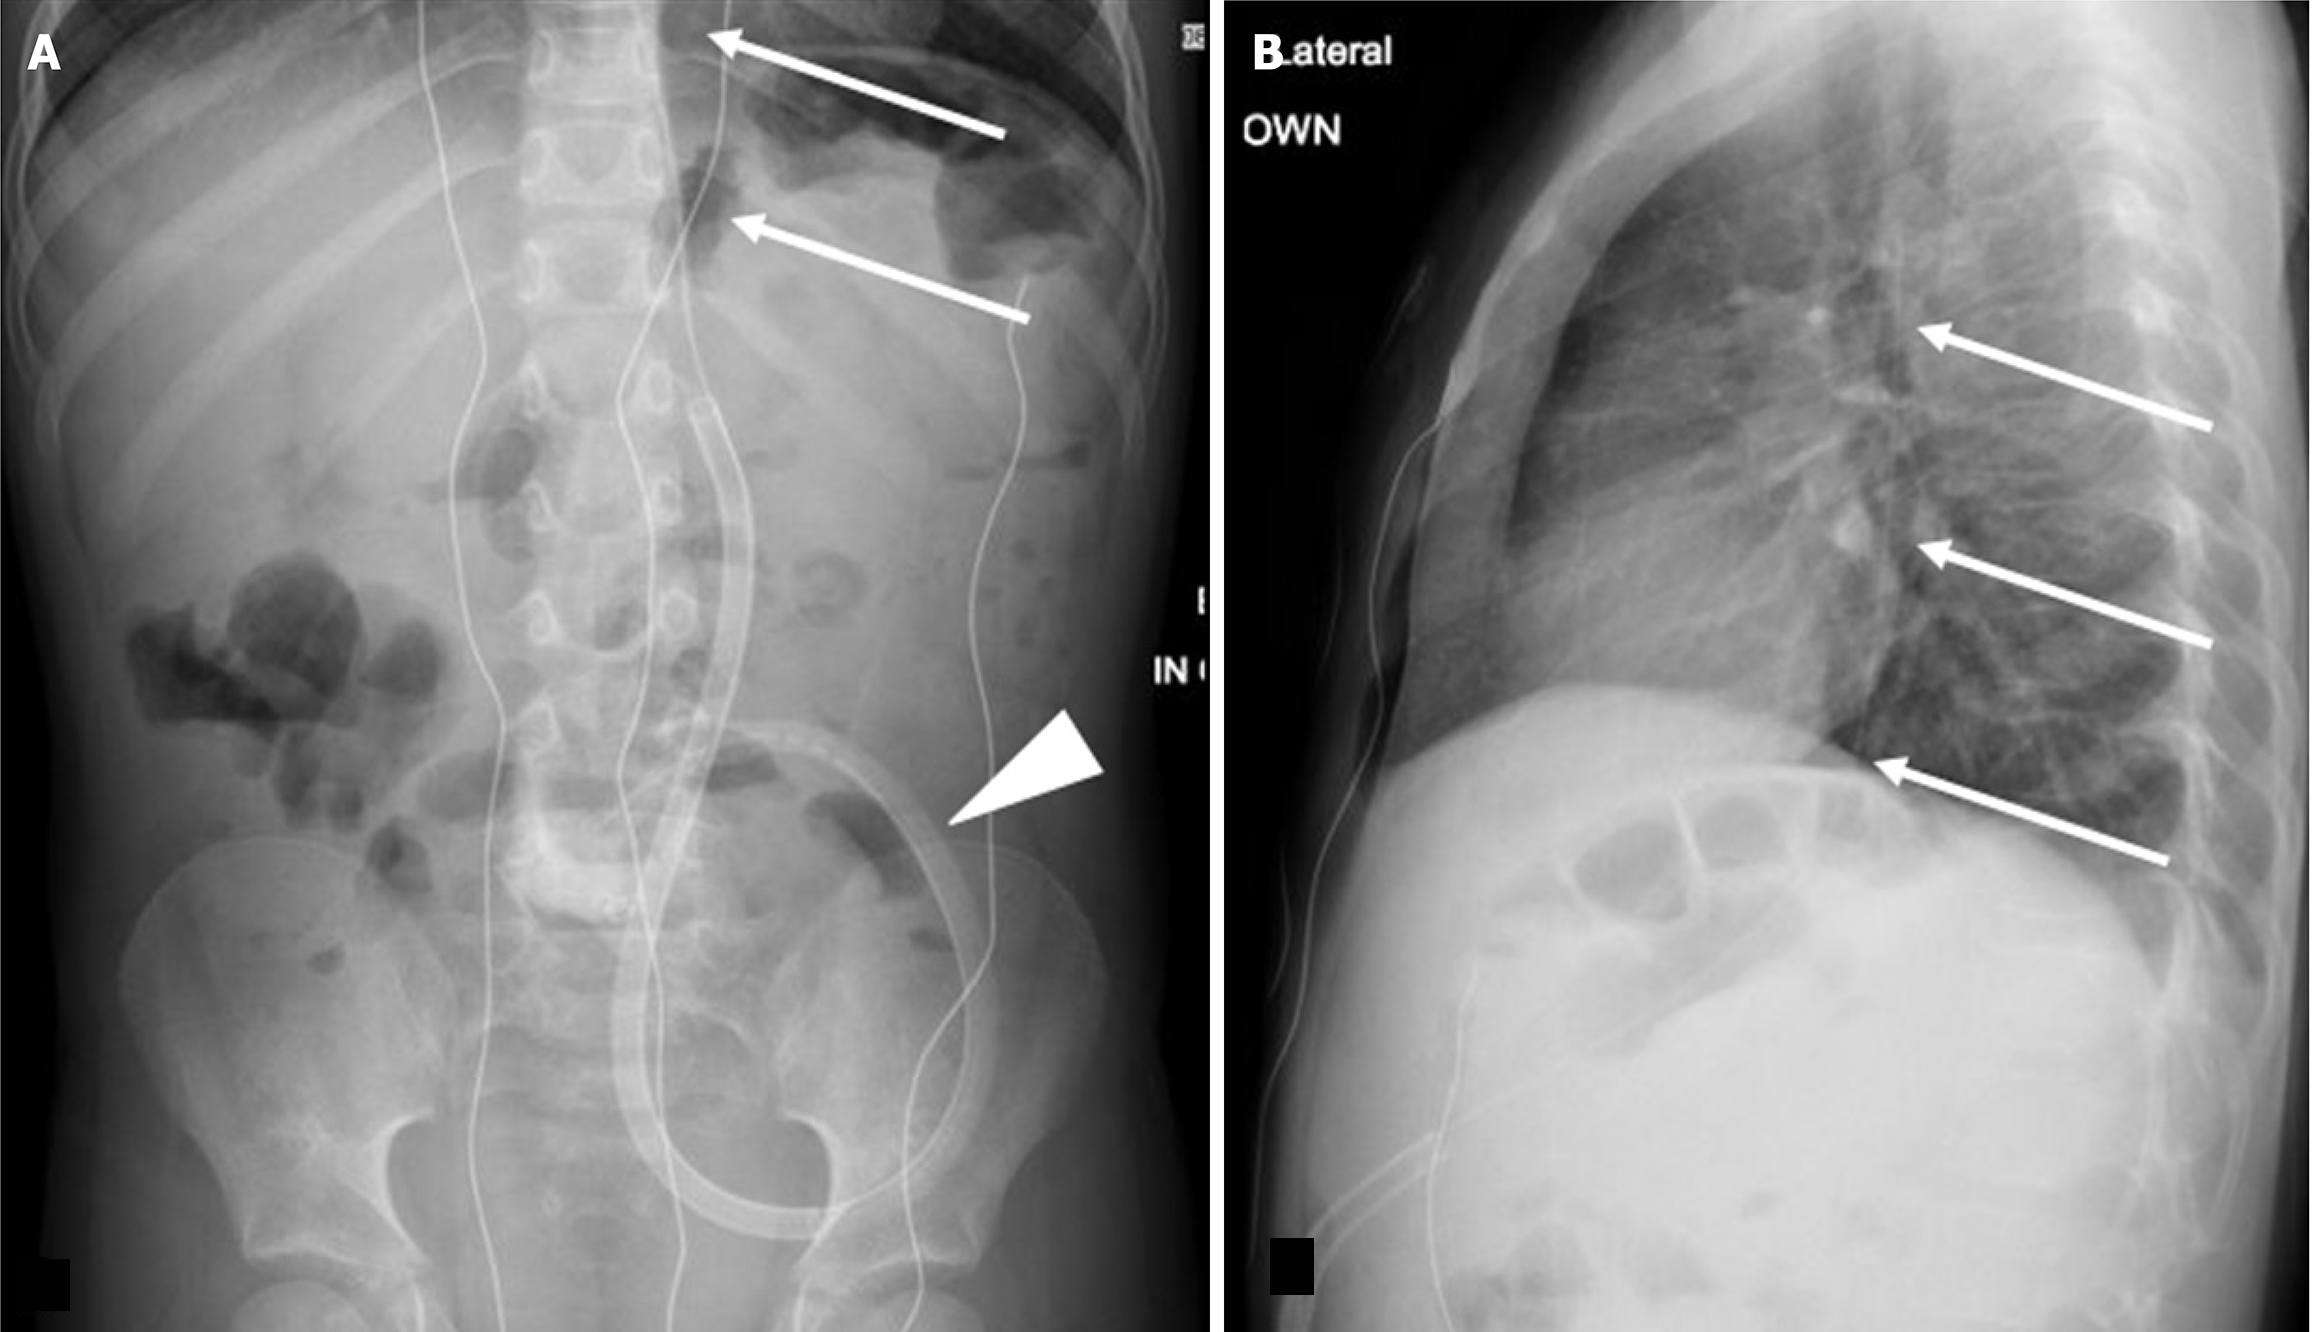

Figure 8 Retraction of gastrojejunostomy tube into the stomach identified incidentally on scoliosis radiographs.

A: Frontal; B: Lateral spine radiographs. They show retraction and coiling of the gastrojejunostomy tube (arrows) into the stomach without a retroperitoneal course; C: Frontal abdominal radiographs of the same patient 10 days prior demonstrates gastrostomy tube coursing normally along the C-loop of the duodenum (arrowhead).